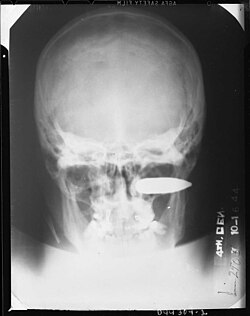

Depiction of a gunshot wound of the brain. (WC/National Library of Medicine)

X-rays are useful for locating bullets. (WC)

Evidence

• Bullets are often good evidence:

• The calibre (size) and markings from the barrel (on handgun/rifle projectiles) allow it to be matched to the weapon that fired it.

• Thus, all projectiles are recovered from a body... and it is routine to X-ray all gunshot victims.